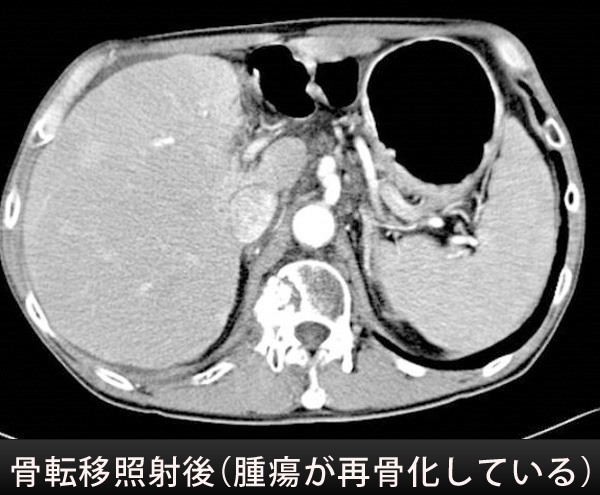

- 機能形態温存

放射線治療の特徴の一つが機能形態温存です。放射線は、何回にも分割して照射することで、がん細胞だけを殺し、正常細胞を温存することができます。この性質を利用して、正常臓器の機能や形態を犠牲にせずに、がん組織だけを抑え込むことを狙います。

がんによる痛みなどの症状を緩和する目的の放射線治療です。鎮痛剤と異なり、痛みの根本原因を治療するので、副作用は少なく効果は強力です。

熊本大学病院放射線治療科では、地域がん診療連携拠点病院として、他の診療科や地域の医療機関と連携し、緩和的放射線治療にも力を入れています。